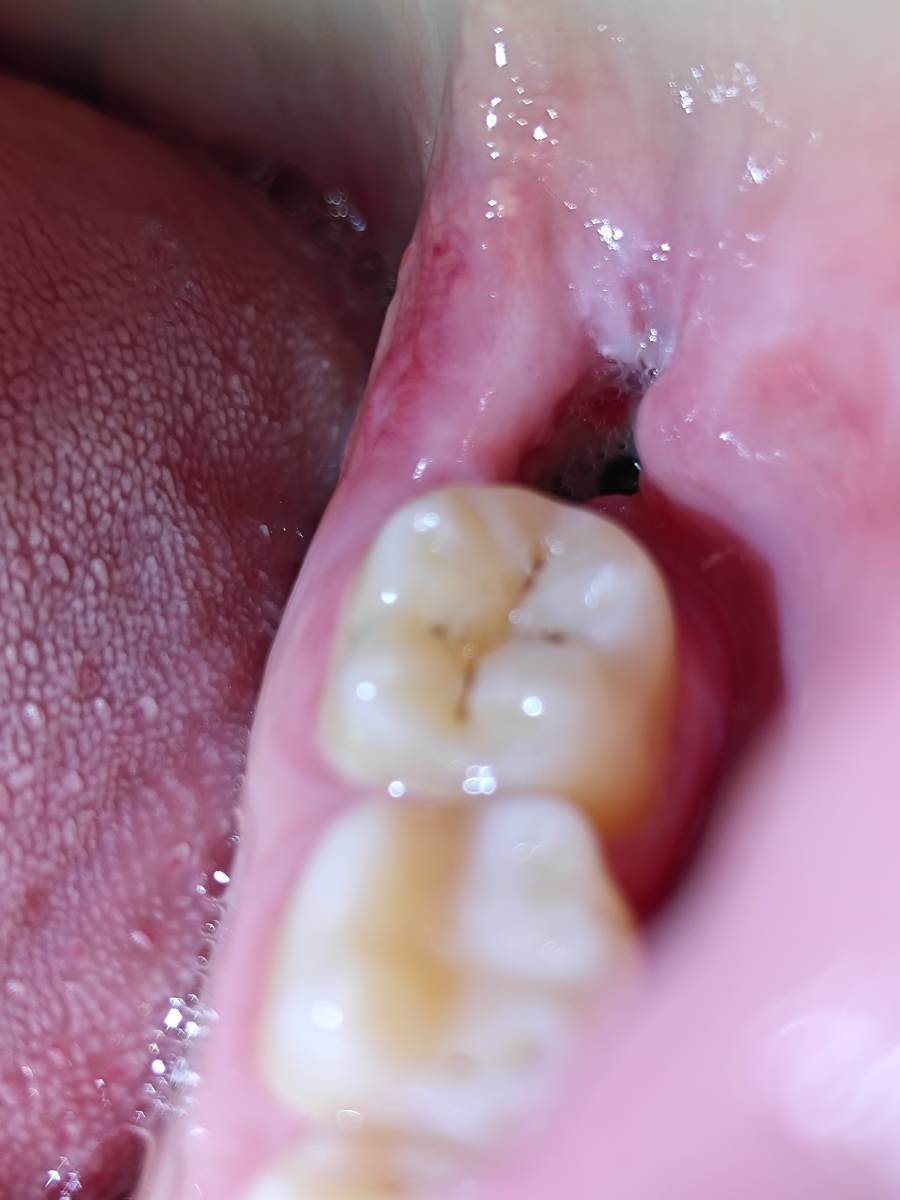

Всем привет, коллеги! 14 лет, терапевты ставят трещину по КТ (снимков до, к сожалению нет, косяк, каюсь). чуть сепарировав зуб и глянув на зуб под отлетевшим куском пломбы трещина "подтвердилась". Кейс на фото. Из интересного - маленький реколл в 1.5 года и спокойное перемещение зуба брекетами!